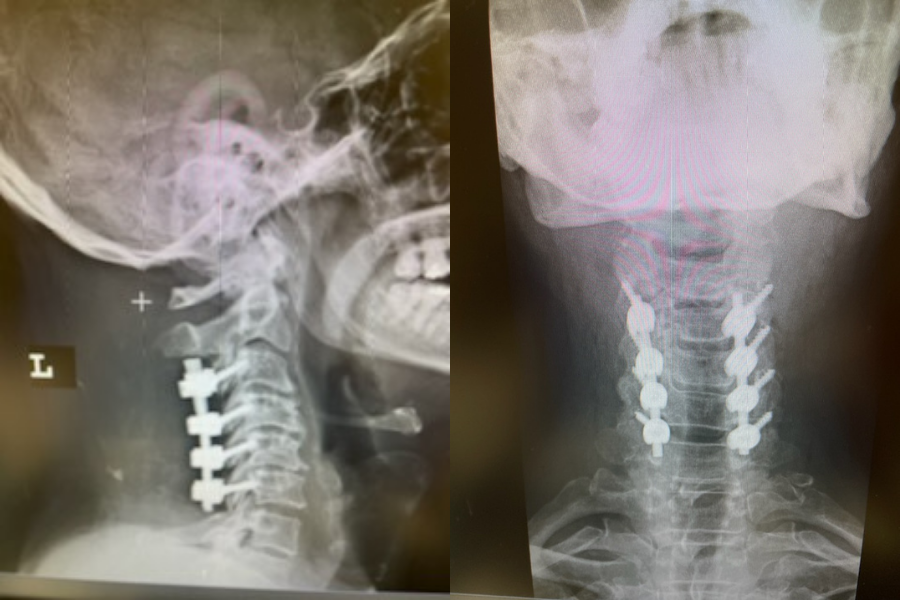

This 57 year-old male presents with severe neck, left shoulder and arm pain and weakness in his hand since being involved in a motor vehicle accident nine months prior. The patient had subsequent left shoulder surgery although he still complained of pain postoperatively and his weakness persisted. He was on no blood thinners. He underwent imaging. The cervical spine MRI revealed an extensive dorsal epidural collection from C1-2 through C5 with associated spinal cord compression. In addition there were multisegmental degenerative changes with foraminal stenosis worse at C4-5 (Fig. 1a and 1b).

(1a) Sagittal and axial T2-weighted cervical MRI demonstrating extensive dorsal epidural collection with hyperintense signal consistent with fluid causing spinal cord compression.

(1b) Hyperintense signal (arrow) at the C3-4 interspinous space consistent with ruptured interspinous ligament,C4-5 (Fig. 1a and 1b).

The fluid was possibly consistent with CSF versus chronic hematoma. The patient was also noted to have a high signal within the interspinous space of C3-C4. This high signal was consistent with a ruptured C3-4 interspinous ligament. Cervical flexion-extension x-rays demonstrated 6 mm of widening of the C3-4 interspinous space on flexion x-ray consistent with cervical instability (Fig. 2a and 2b).